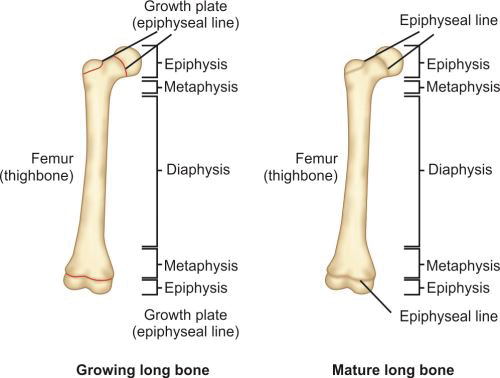

Epiphyseal plate/growth plate or physis: Hyaline cartilage present above the proximal metaphysis and below the distal metaphysis separating metaphysis from epiphysis.

Cortical bones are long bones of the body like femur or humerus and the small bones of hand and foot like metacarpals and metatarsals. Long bones of a child (Fig. 1.12) are divided into epiphysis, physis or growth plate, metaphysis and diaphysis. Epiphysis, physis and metaphysis are present at both ends. In mature bone epiphysis fuses with metaphysis and growth plate gets replaced by bone.

Parts of a growing long bone:

-

Epiphyses: Epiphyses are present on the ends of the bones. It consists of cancellous bone covered by a thin layer of compact bone. On its ends it is covered by articular cartilage and forms the joint. In long bones epiphysis is present on both the ends; it is present on only one end of metacarpal, meta-tarsals and phalanges.

-

Physes: Physis or growth plate is a thin region of actively growing bone cells between the epiphysis and the metaphysis in a growing bone. This is present on both the end of the long bones and responsible for the longitudinal growth of the bones. It consists of four zones (Fig. 1.13):

- Germinal zone/Resting zone

- Proliferative zone

- Hypertrophic zone

- Zone of endochondral ossification.

Germinal zone provides the developing chondrocytes which divide and get organized into columns in proliferative zone. Both germinal and proliferative zones are rich in extracellular matrix. In hypertrophic zone chondrocytes stop mitoses and undergo hypertrophy. This is the weakest zone of physis and most physeal injuries occur through this plane.

Physis is connected to epiphysis and metaphysis by the zone of Ranvier and perichondral ring of LaCorix. Zone of Ranvier contains germinal cells, which is responsible for circumferential growth of physis. Ring of LaCorix is a fibrous structure that is connected with zone of Ranvier and periosteum of metaphysis.

-

Metaphysis: It is the junction between the growth plate and the diaphysis. It consists of both cancellous and cortical bone.

-

Diaphysis: It is the region between the two metaphyses. It consists of compact cortical bone and has a medullary canal which consists of marrow. This portion of the bone is responsible for the strength of bone for weight bearing and movement.